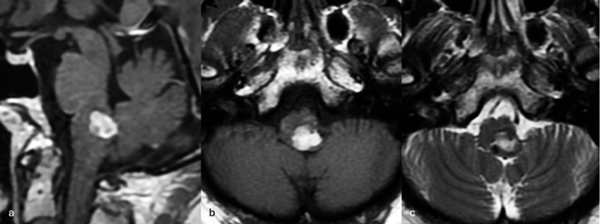

Figura 3. RM preoperatoria de encéfalo. Se evidencia una lesión única intraaxial centrada en puente y pedúnculo cerebeloso derecho, sugerente de un cavernoma roto. A, B y C) Imágenes ponderadas en T2 en cortes sagital, axial y coronal, respectivamente, donde se observa un importante hiperintensidad perilesional, sugerente de edema.

Figura 6. RM preoperatoria de encéfalo. Se evidencia una lesión única intraaxial localizada en el puente y pedúnculo cerebeloso medio izquierdo, hiperintensa en T1 y con un anillo hipointenso en T2, característica de una malformación cavernomatosa con sangrado reciente. A) Imagen ponderada en T1 en corte sagital. B y C) Imágenes ponderadas en T2 en cortes axial y coronal, respectivamente.